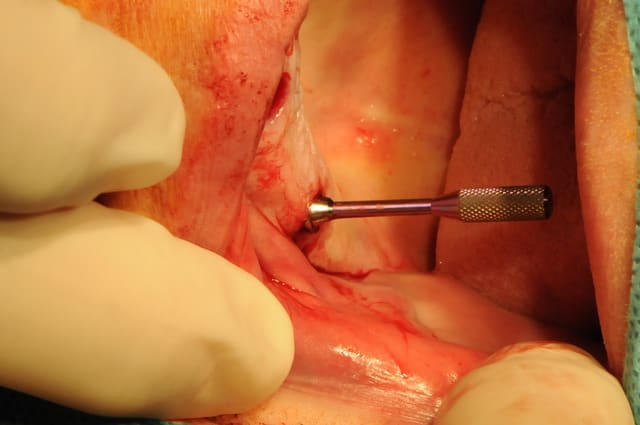

la patiente a été opérée hier et j'ai mis ses prothèses aujourd'hui.

la veille de l'intervention j'ai imprimé le model 3 D.

je remercie Rachel et Arnaud qui se sont prêtés à la délicate tâche de l'assistante opératoire.